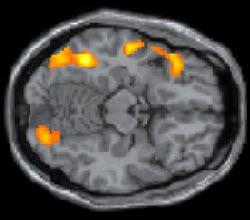

La tecnología ha evolucionado pero nuestro cerebro no lo ha hecho.Para la Biología 6000 años son muy pocos años desde el punto de vista evolutivo. El amigo lector que lee ahora mismo este texto está usando los mismos mecanismos neuronales que los que usaba un aprendiz de escriba hace miles de años al leer, a orillas del Nilo, un papiro con las oraciones dedicadas a algún dios tenebroso.Si tenemos esa capacidad de leer es porque nuestro cerebro es lo suficientemente flexible como para dedicar ciertas partes de él, que normalmente se dedican a otras tareas, para que sirvan a la lectura. Pero, ¿qué partes son esas?Para investigar este asunto Stanislas Dehaene, junto con otros compatriotas franceses y colaboradores de Bélgica, Portugal y Brasil, ha estudiado la actividad cerebral de 63 voluntarios entre los que había 31 que aprendieron a leer de pequeños, 22 que aprendieron de adultos y 10 que eran analfabetos

Aquellos que leían, independientemente de cuándo aprendieron a hacerlo, exhibían una respuesta más intensa a las palabras escritas en varias regiones cerebrales encargadas del procesamiento visual.Basándose en trabajos previos, estos investigadores sostienen que una de estas regiones, la unión de los lóbulos occipital y temporal es especialmente importante en la lectura. Además, en las personas que sabían leer (pero no en los demás), las palabras escritas disparaban actividad cerebral en el lóbulo temporal que es responsable del lenguaje. Esto sugiere que la lectura usa circuitos cerebrales relacionados con el lenguaje hablado, una innovación mucho más antigua en la comunicación humana que la escritura.Según Dehaene tiene sentido que la lectura descanse en regiones cerebrales que originalmente evolucionaron para procesar la visión y el lenguaje hablado. Pero, a cambio, este logro tiene un costo. Los investigadores encontraron que, en las personas que aprendieron a leer de pequeños, la parte del córtex temporal occipital dedicada al reconocimiento facial es más pequeña que en los analfabetos. Dehaene sugiere que la lectura debe de competir por el acceso a esta parte del cerebro con otras tareas, como la percepción facial. Si es así puede que la lectura haga que la gente reconozca peor las caras. Estos mismos investigadores ya están realizando experimentos al respecto.

Los hallazgos avalan la idea de Dehaene de que el córtex temporal occipital es una región donde el cerebro experimenta adaptaciones importantes para procesar el lenguaje escrito.Según Brian Wandell, de la Universidad de Stanford y no involucrado en este estudio, el cerebro se hace más flexible con la edad, así que sería interesante saber si esta región cambia cuando las personas aprenden a leer de adultos .En todo caso, espero que el amigo lector haya podido viajar un poquito con su imaginación, gracias a este texto, por los vericuetos de nuestro cerebro.